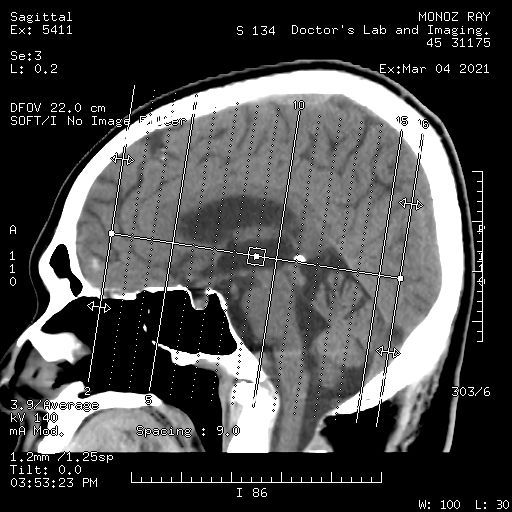

diagnostic and imaging